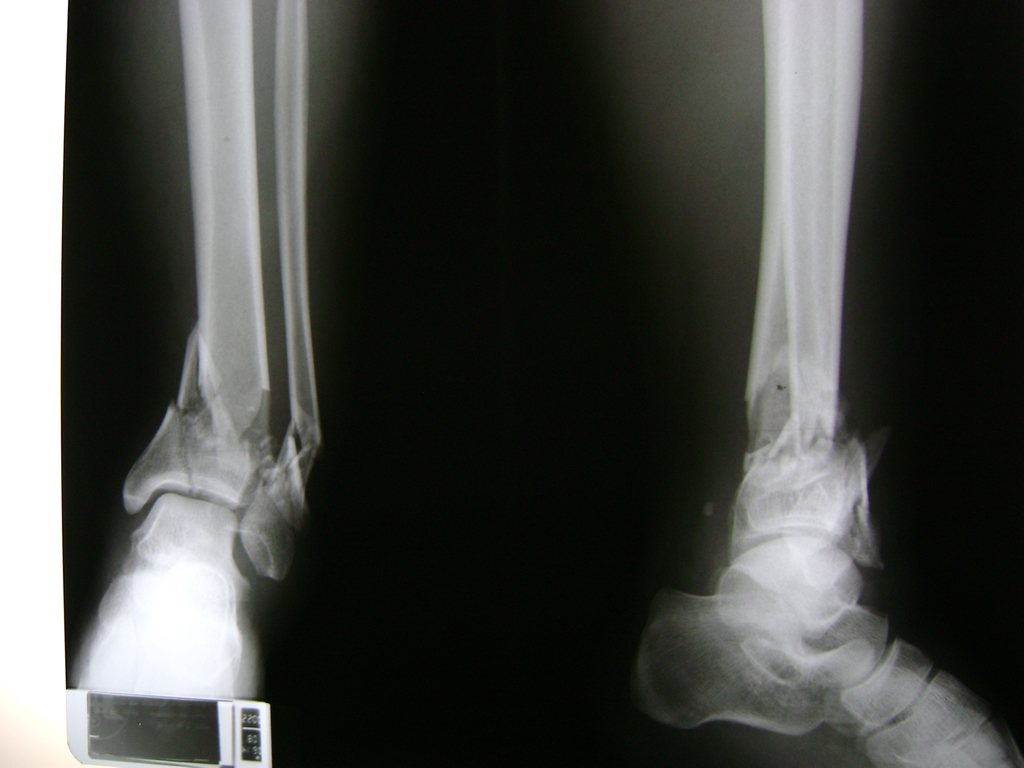

Algunas fracturas de tobillo pueden requerir cirugía si:

- Los extremos de los huesos están desalineados entre sí (desplazados).

- La fractura se extiende hasta la articulación del tobillo (fractura intra-articular).

- Los tendones o ligamentos (tejidos que sujetan los músculos y los huesos entre sí) están rotos.

- El médico cree que sus huesos probablemente no sanen apropiadamente sin cirugía.

- El médico considera que la cirugía puede permitirle una recuperación más rápida y confiable.